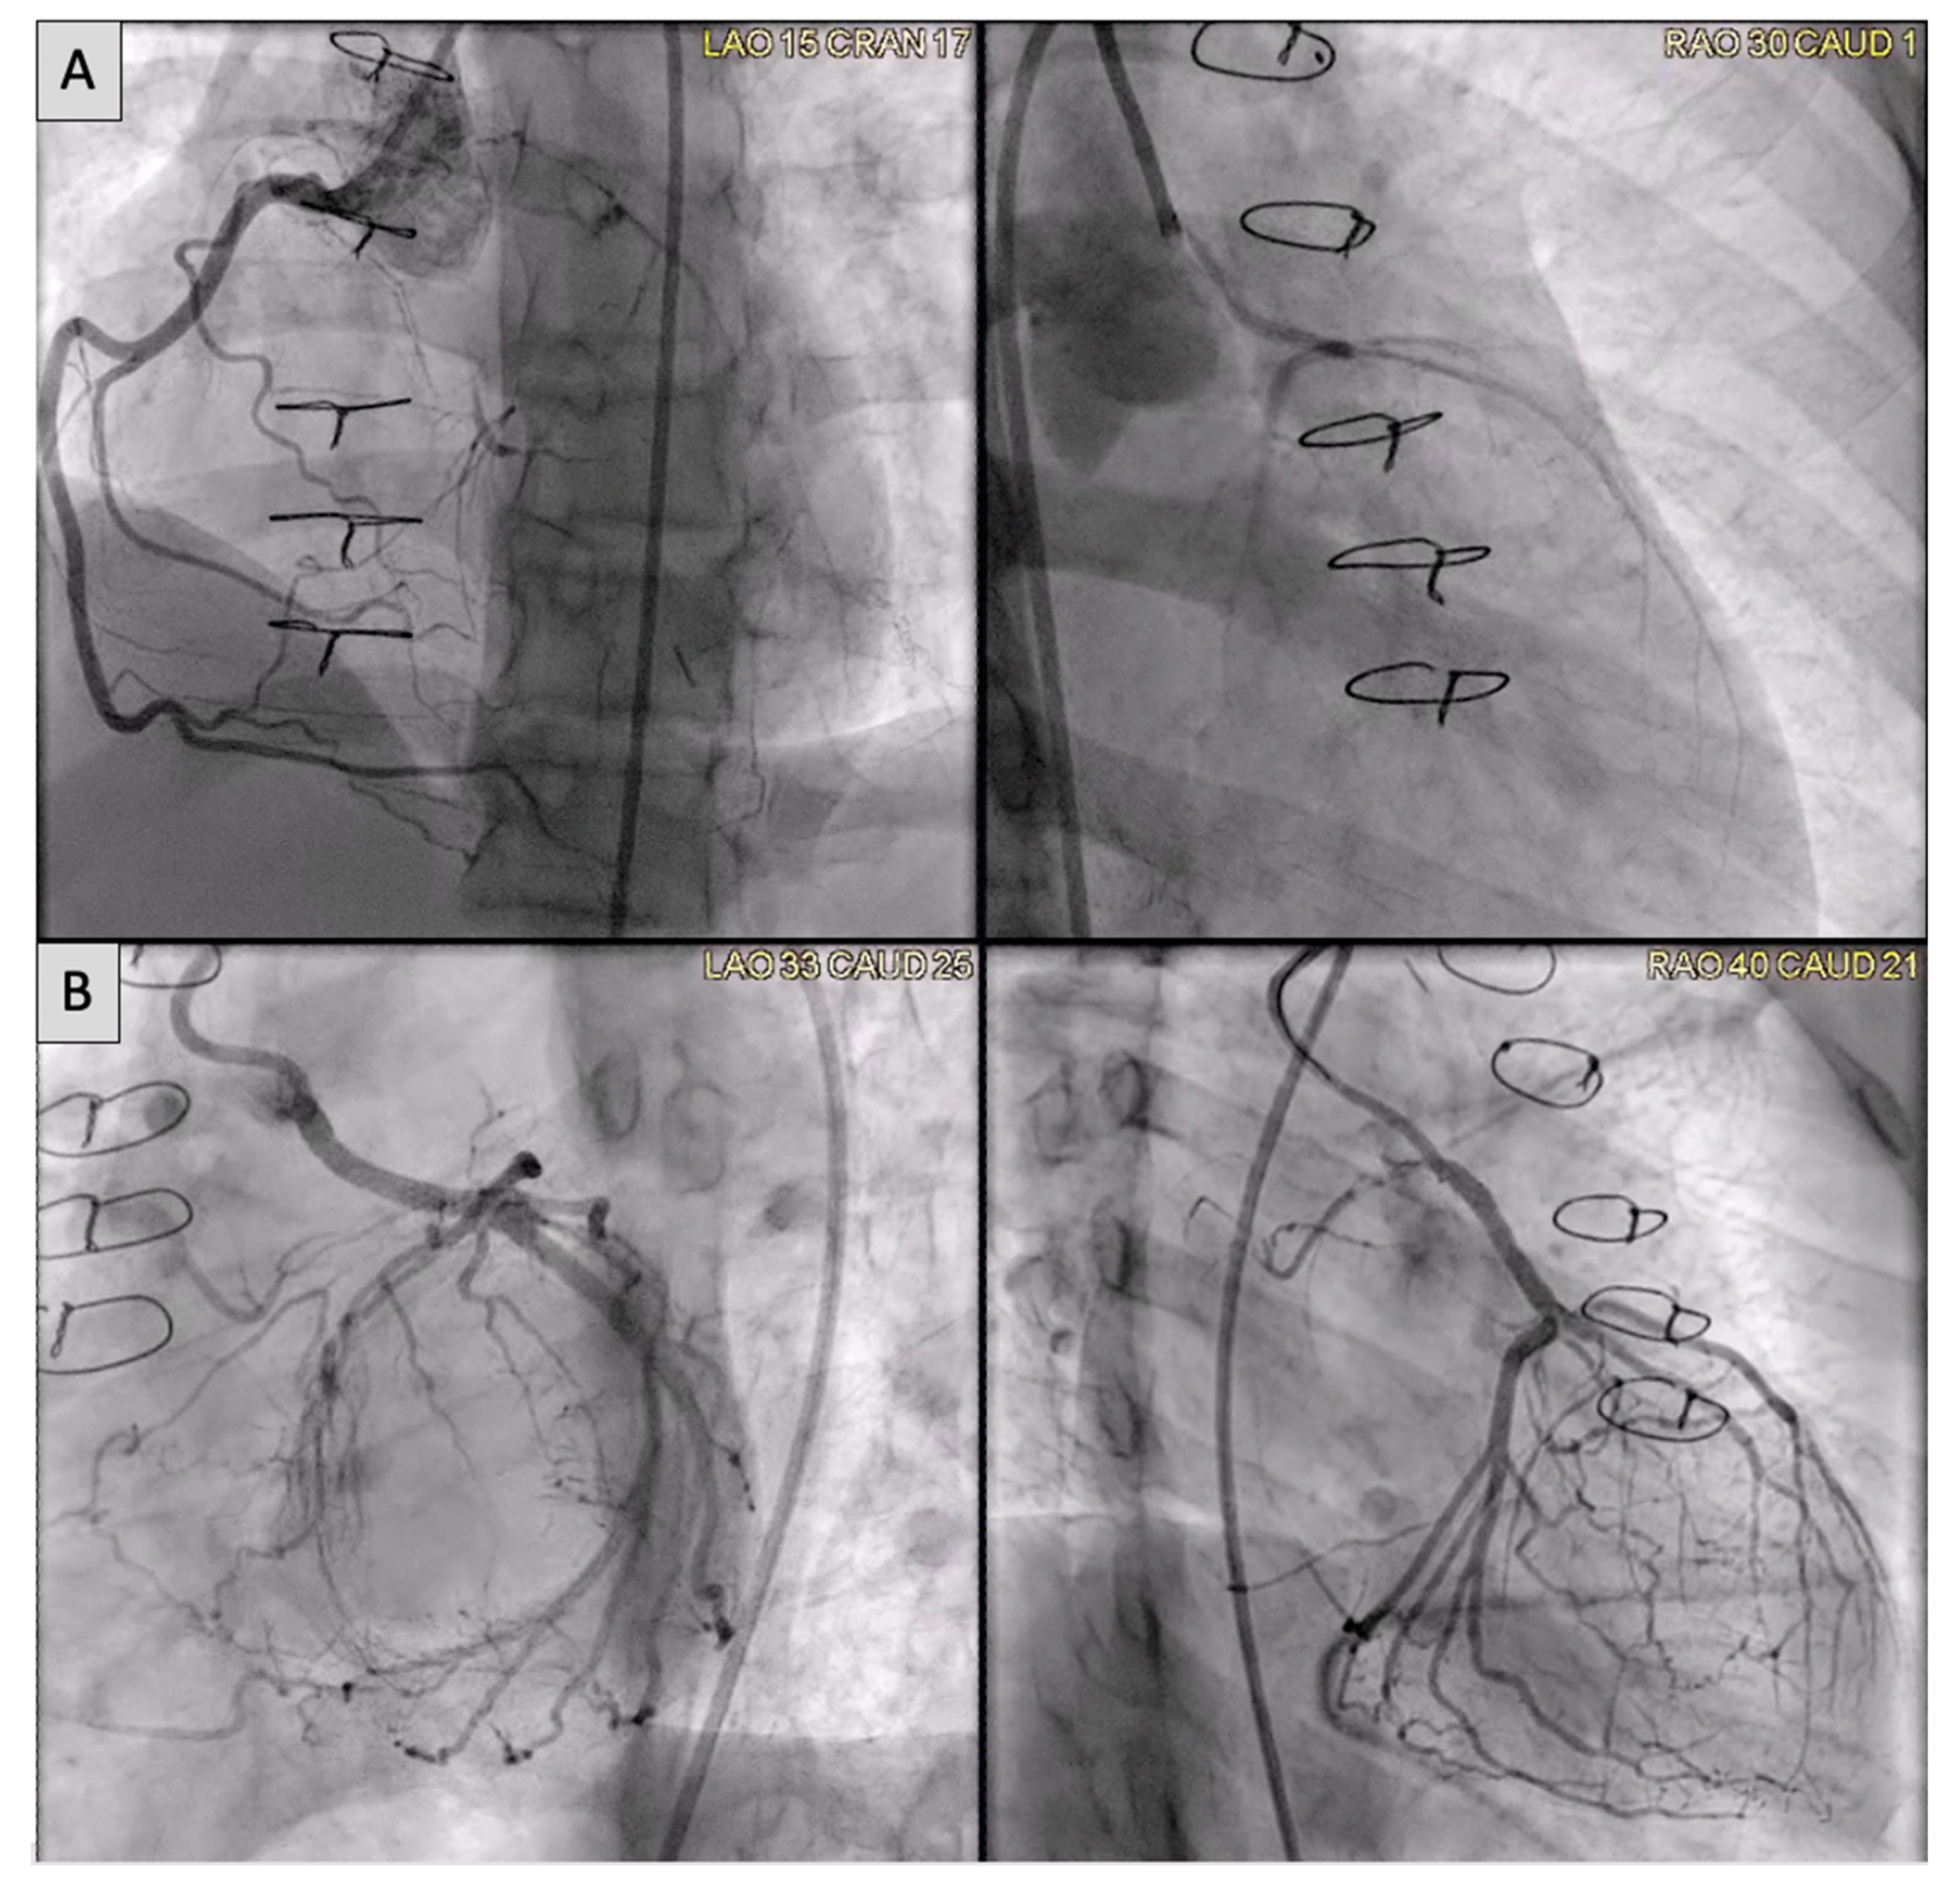

2.5. Coronary Artery Assessment in CHD